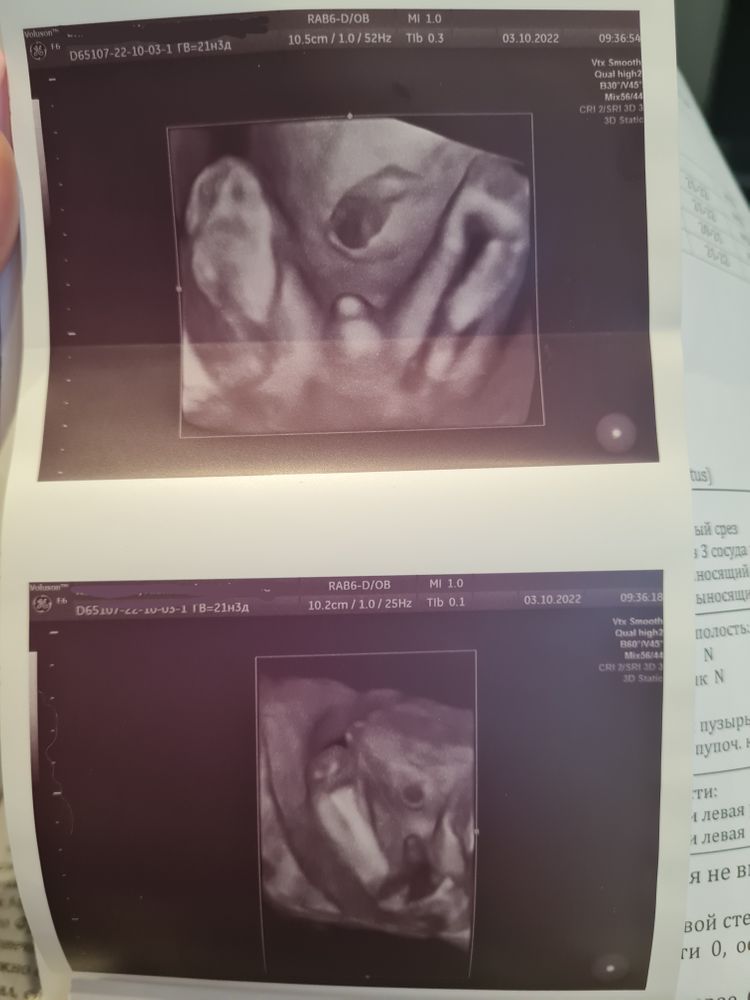

3) Про замеры малыша и пол вообще интересно. Пока все 4 разных доктора мне хором не сказали про мальчика - ничему не верила, знаем мы прецеденты))

Последний, так вообще - первые минут 10 делал мне фото писюна в разных ракурсах и проекциях (и 3D, и просто узи). Смешно)) Врачом мужчина был, кстати.

По замерам вроде бы все нормально, в нормах. Меня конечно нервировал СД (ну мы уже не молодые, чо) и разные отклонения по сердцу (клапаны там, перегородки). И Спина Бифида тоже волнует, но тоже вроде ттт, последний врач прям показывал мне позвоночник отдельно детально. Аргумент про возраст и хт сделал свое дело.

Велели прийти в 24 недели пересмотреть сосуды вокруг сердца, все должно подрасти и быть более четким.

Вот вам фото писюна, вдруг кому интересно как он выглядит в 21 неделю)))